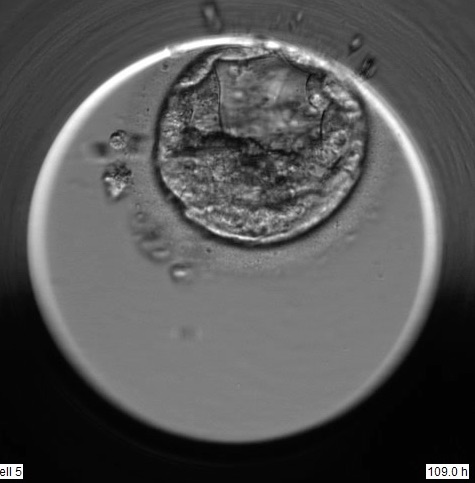

Ich habe drei Entwicklungsstadien aus dem Film abgebildet. 1. Foto 48 Stunden, 2. Foto 69 Stunden und letztes Bild nach 109 Stunden.

Den Embryo an d5 würde ich mit 1BB einstufen d.h. eine BC, deren Strukturen

beginnen, sich gut auszubilden und gute Voraussetzungen für die weitere Entwicklung zeigen.